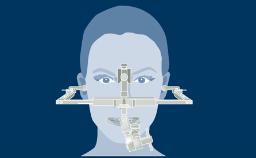

种植体植入应遵循的修复设计原则

无论治疗的位置或程度如何,种植治疗计划应始终以修复为导向。这可确保种植体植入满足义齿的需求,并与期望的最终效果相一致。为了实现最佳的效果,修复计划应包括:考量所有相关修复因素,并进行适当的诊断检查,在此基础上制定种植义齿和支持种植体的具体计划。